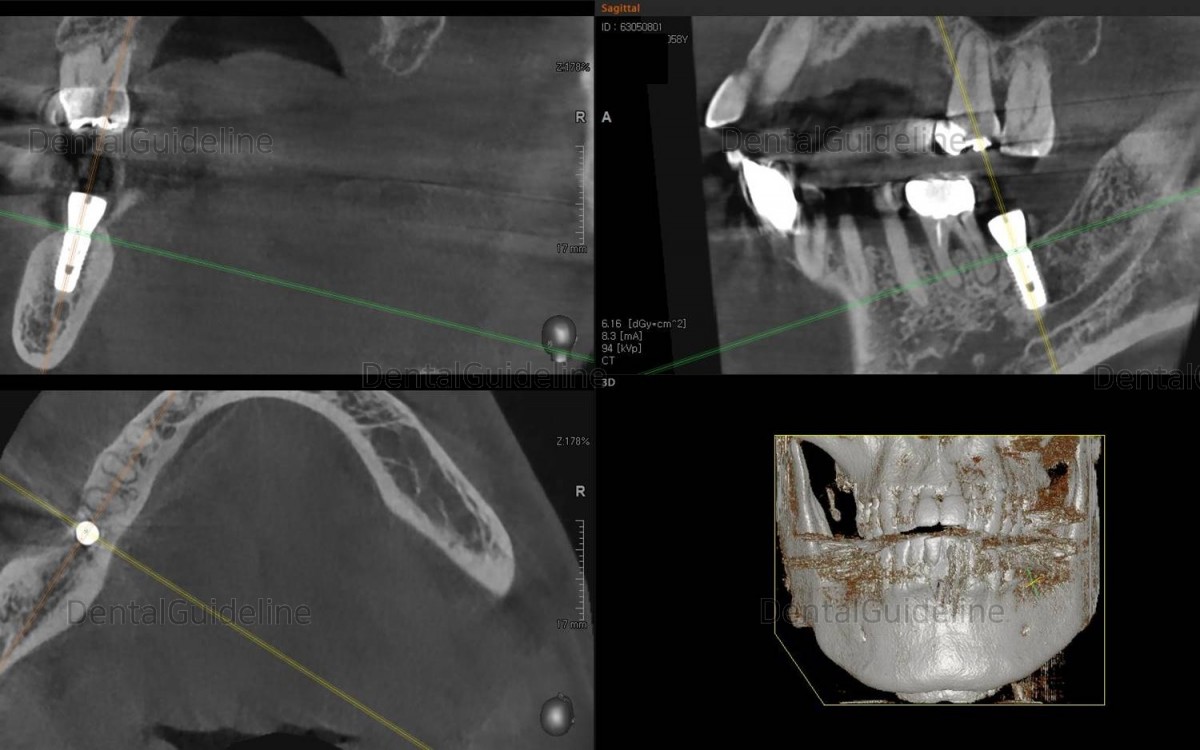

Rough simulation on the CBCT scan image.

The size, length, and position of the implant were simply checked.